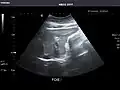

Kidneys: Right and left kidneys measure 11.5 cm and 12 cm in length respectively. No hydronephrosis. Small left lower pole kidney cyst.

Right kidney -

Left kidney -